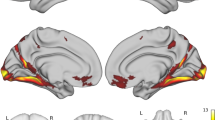

Structural MRI

While we observed typical negative associations between hippocampal volume (mm3) and age at scan (t = − 2.40, P = 0.039), we observed no evidence for difference in hippocampal volume between the AD-PRS groups (P > 0.3). The high AD-PRS group reported significantly reduced cingulate thickness (mm), corrected for age, sex, and total cortical thickness (Figs. 2B and 3B; Cohen’s d = − 1.55 [95% − 2.75, − 0.30], PFDR = 0.050). This association was further present in the sub-sample of APOE ε3ε3 carriers (t = − 3.19, P = 0.019).

We observed that for the RbG sample and within the cingulate cortex, the thickness of the region cytoarchitecturally defined as the right anterior caudal cingulate cortex was most nominally associated with AD-PRS (β = − 0.21 ± 0.084, PUNCORRECTED = 0.032). We therefore acquired the summary statistics for a comparable GWAS from UK Biobank (Image Derived Phenotype ID: 1056 (aparc-Desikan_rh_thickness_caudalanteriorcingulate). We replicated this observation in this UKBB sample (N = 31,966; β = − 0.002 ± 0.001, PREPLICATION = 0.011) (Fig. 4).

Within the cingulate cortex, the sub-region most associated was the right caudal anterior cingulate. The negative association between AD-PRS and right caudal anterior cingulate thickness in the recall-by-genotype (RbG) was replicated in the UK BioBank (UKBB) sample (N = 31,966). Y-axis represents beta estimates. Error bars represent 95% confidence intervals of the beta estimate

The participants with a high AD-PRS showed marked reductions in (i) autobiographical memory and (ii) cingulate thickness compared to the low AD-PRS group. However, we did not observe an association between AD-PRS and hippocampal volume, suggesting the shared variance may be smaller than our study power afforded or that associations may be explained by confounding from genetically correlated traits such as intelligence/years of education. Several studies have demonstrated a negative association between AD-PRS hippocampal volume across the lifespan [14, 17, 35, 36]; however, a significant proportion of the shared variance has been attributed to an association with the APOE locus [14, 42]. Our study broadly conforms to two prior observations. First, a substantial body of evidence has previously demonstrated that increased AD genetic risk is linked to reduced cognition, with studies showing negative genetic correlations between cognition and AD common variants and AD-PRS studies supporting this observation. Second, this study supports prior observations that cortical thickness of midline / cingulate structures are reduced in individuals with high AD-PRS [37]. More specifically, reduced anterior cingulate thickness has previously been linked to AD genetic risk within a endocytosis pathway-specific AD-PRS analysis [43], across MCI groups and via associations with meta-memory in AD [44]. More recently, a negative association between AD-PRS and caudal anterior cingulate thickness has further been demonstrated in a large, pre-pubescent sample (NABCD > 4000), suggesting that this alteration may be a risk factor that is expressed across the lifespan [45]. While the sample age range (58–76) and autobiographical memory assessment deficit do not allow us to delineate between prodromal and early disease effects [46], we suggest that the assays we report are an initial showcase of the ability to detect AD-PRS-related differences in significantly smaller samples that could be employed at point in the lifespan, using biological readouts that are more complex and not scalable in large samples / cohorts. While we observed converging evidence linking AD-PRS with cingulate thickness, the study must be considered with the following limitations. While the sample size provided > 80% power to detect an association with AD-PRS, a larger or replication sample would have allowed us to further assess the validity of our findings. While this was not possible for the Survey of Autobiographical Memory (SAM), we did replicate the negative association between AD-PRS and cingulate thickness in a larger sample (N = 31,966). Here, we used a larger AD GWAS dataset to estimate AD-PRS [41], which became available after recruitment, an advantage of working with secondary data and updated GWAS derivates, compared to our recall-by-genotype study, which was constrained by AD-PRS estimations made before recruitment (see last section of the limitations section within this discussion). The effect size of this association was considerably smaller, this is however to be expected in a sample with additional potential sources of confounding and heterogeneity [47]. Second, we did not have a comparable group with an average AD-PRS (for example, participants with an AD-PRS in a middle decile). Therefore, any group differences we observe here may reflect higher SAM and thickness in the very low AD-PRS group, rather than preclinical alterations in the high AD-PRS group. Third, we also acknowledge that the cross-sectional design does not reveal important information such as MCI / AD conversion or trajectories which would have helped to establish the utility of the observed features in the prediction of future neurodegeneration. Fourth, while individual AD-PRS can be considered in relation to the larger sample from which they were derived, it is currently a challenge to provide an individual context about their AD-PRS as a standardised assessment. Future studies of AD-PRS working towards increased portability and generalisability, so individuals’ genetic risk can be considered independent from the sample from which their AD-PRS were estimated, may prove useful for generating AD-PRS based on existing normative samples [5, 6]. Fifth, we acknowledge that AD-PRS only represents a summated total of all known, common AD risk variants. While there are initiatives to assess AD genetic risk via the partitioning of PRS into specific biological pathways, AD-PRS may still reflect a heterogeneous, biologically unspecific estimate, making it difficult to mechanistically implicate specific causal processes. Last, we acknowledge that recall-by-genotype studies using PRS require investigators to recruit on the basis of a specific GWAS data set and with a specific PRS approach (for example, a specific P-threshold, PRS method, and GWAS training data), where variability in the process has the potential to change the position of individuals within the wider recall sample and their respective position in the AD-PRS groups, limiting their flexibility compared to compared to re-analyses of secondary data based on newer AD GWAS derivatives. While ongoing studies are working towards a standardised metric for PRS assessment [48], recall-by-genotype approaches are likely to continue being affected by ongoing GWAS and downstream methods development.